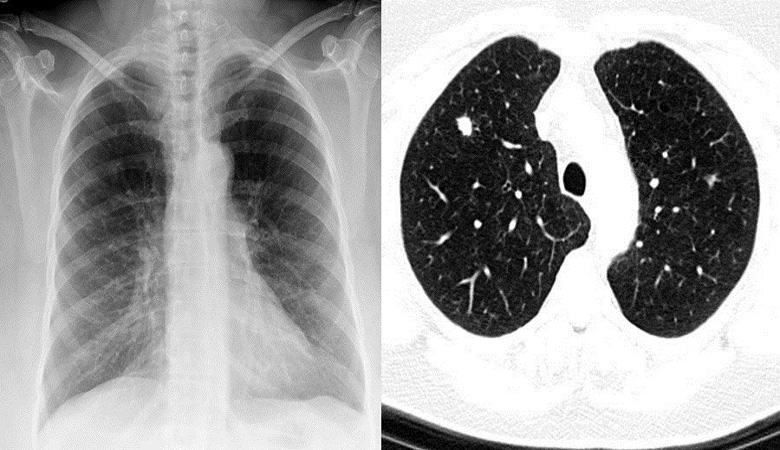

Nel 2016, si aspettava Joe Tippens in pensione dall’Oklahoma tragiche notizie: i medici gli hanno diagnosticato un carcinoma a piccole cellule polmone nell’ultima fase. All’inizio del 2017, metastasi si diffuse in quasi tutto il corpo americano. Compagnia di assicurazioni ma ha speso più di $ 1,2 milioni per curare un uomo inutilmente. Di conseguenza, i medici hanno dato al nostro eroe non più di tre mesi di vita. Ma poi, secondo Tippens, è successo qualcosa veramente incredibile.

oncologia